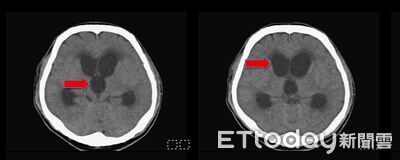

高雄一名48歲油漆工上班時不慎撞到頭造成顱內出血,但他就醫後接受保守治療未開刀,某日突發意識不清,被緊急送往急診室,經過電腦斷層掃描,發現他腦室腫大診斷為「水腦症」,院方立即安排手術引流腦脊髓液,術後男子恢復意識,現也重返工作崗位。醫師強調,腦脊髓液若吸收異常,可能壓迫腦組織,長期恐導致不可逆的神經功能缺損,不可不慎。 《詳全文...》